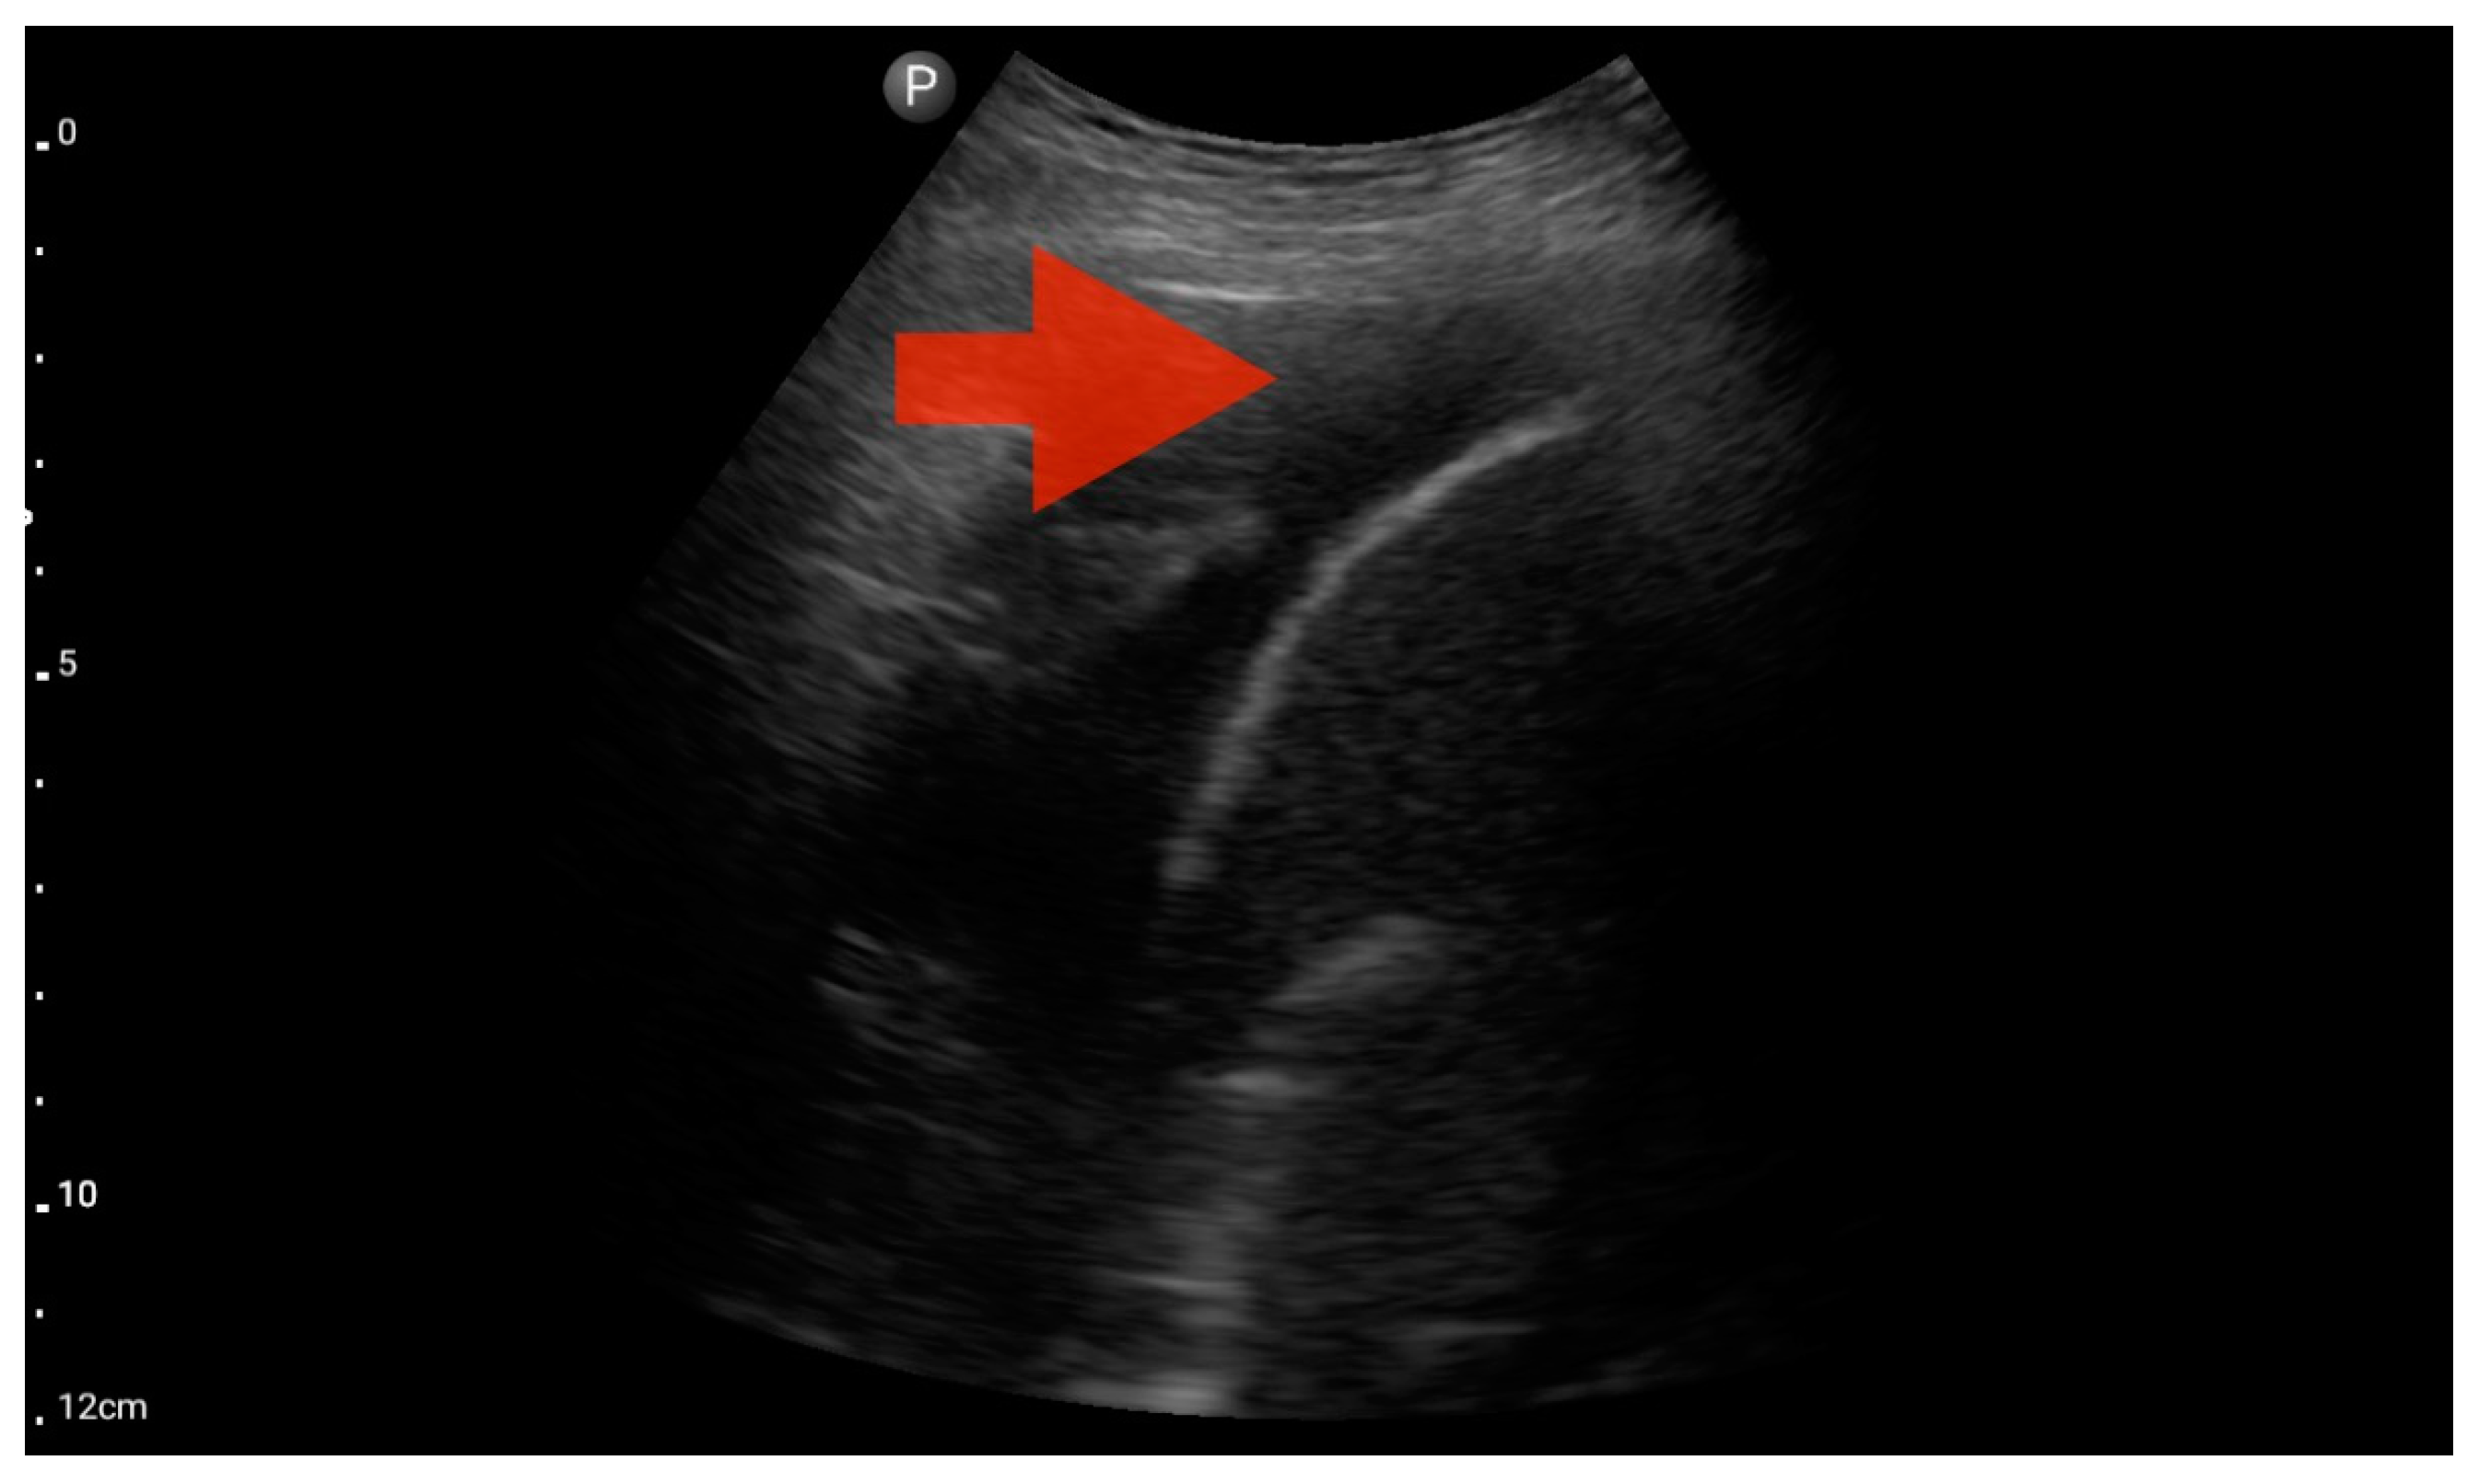

In the assessment according to the BLUE protocol, profile B (Figure 7) was observed in seven (43.75%) patients, profile C (Figure 8) in three (18.75%), and profile B/C (Figure 9) in two (12.5%) patients. Profile A was not detected in the study group. Pleural effusion (Figure 10) was the sole observation in four patients. During the assessment according to the eFAST protocol, no additional features beyond the observed information were found in the study group. Such an assessment seemed to be sufficient in 11 (68.75%) patients.

Figure 11.

Pleural effusion (BLUE protocol). Convex probe examination, the basal part of the lung (pleural recess); the red arrow indicates free fluid in the pleural cavity (source: author’s material—DK).